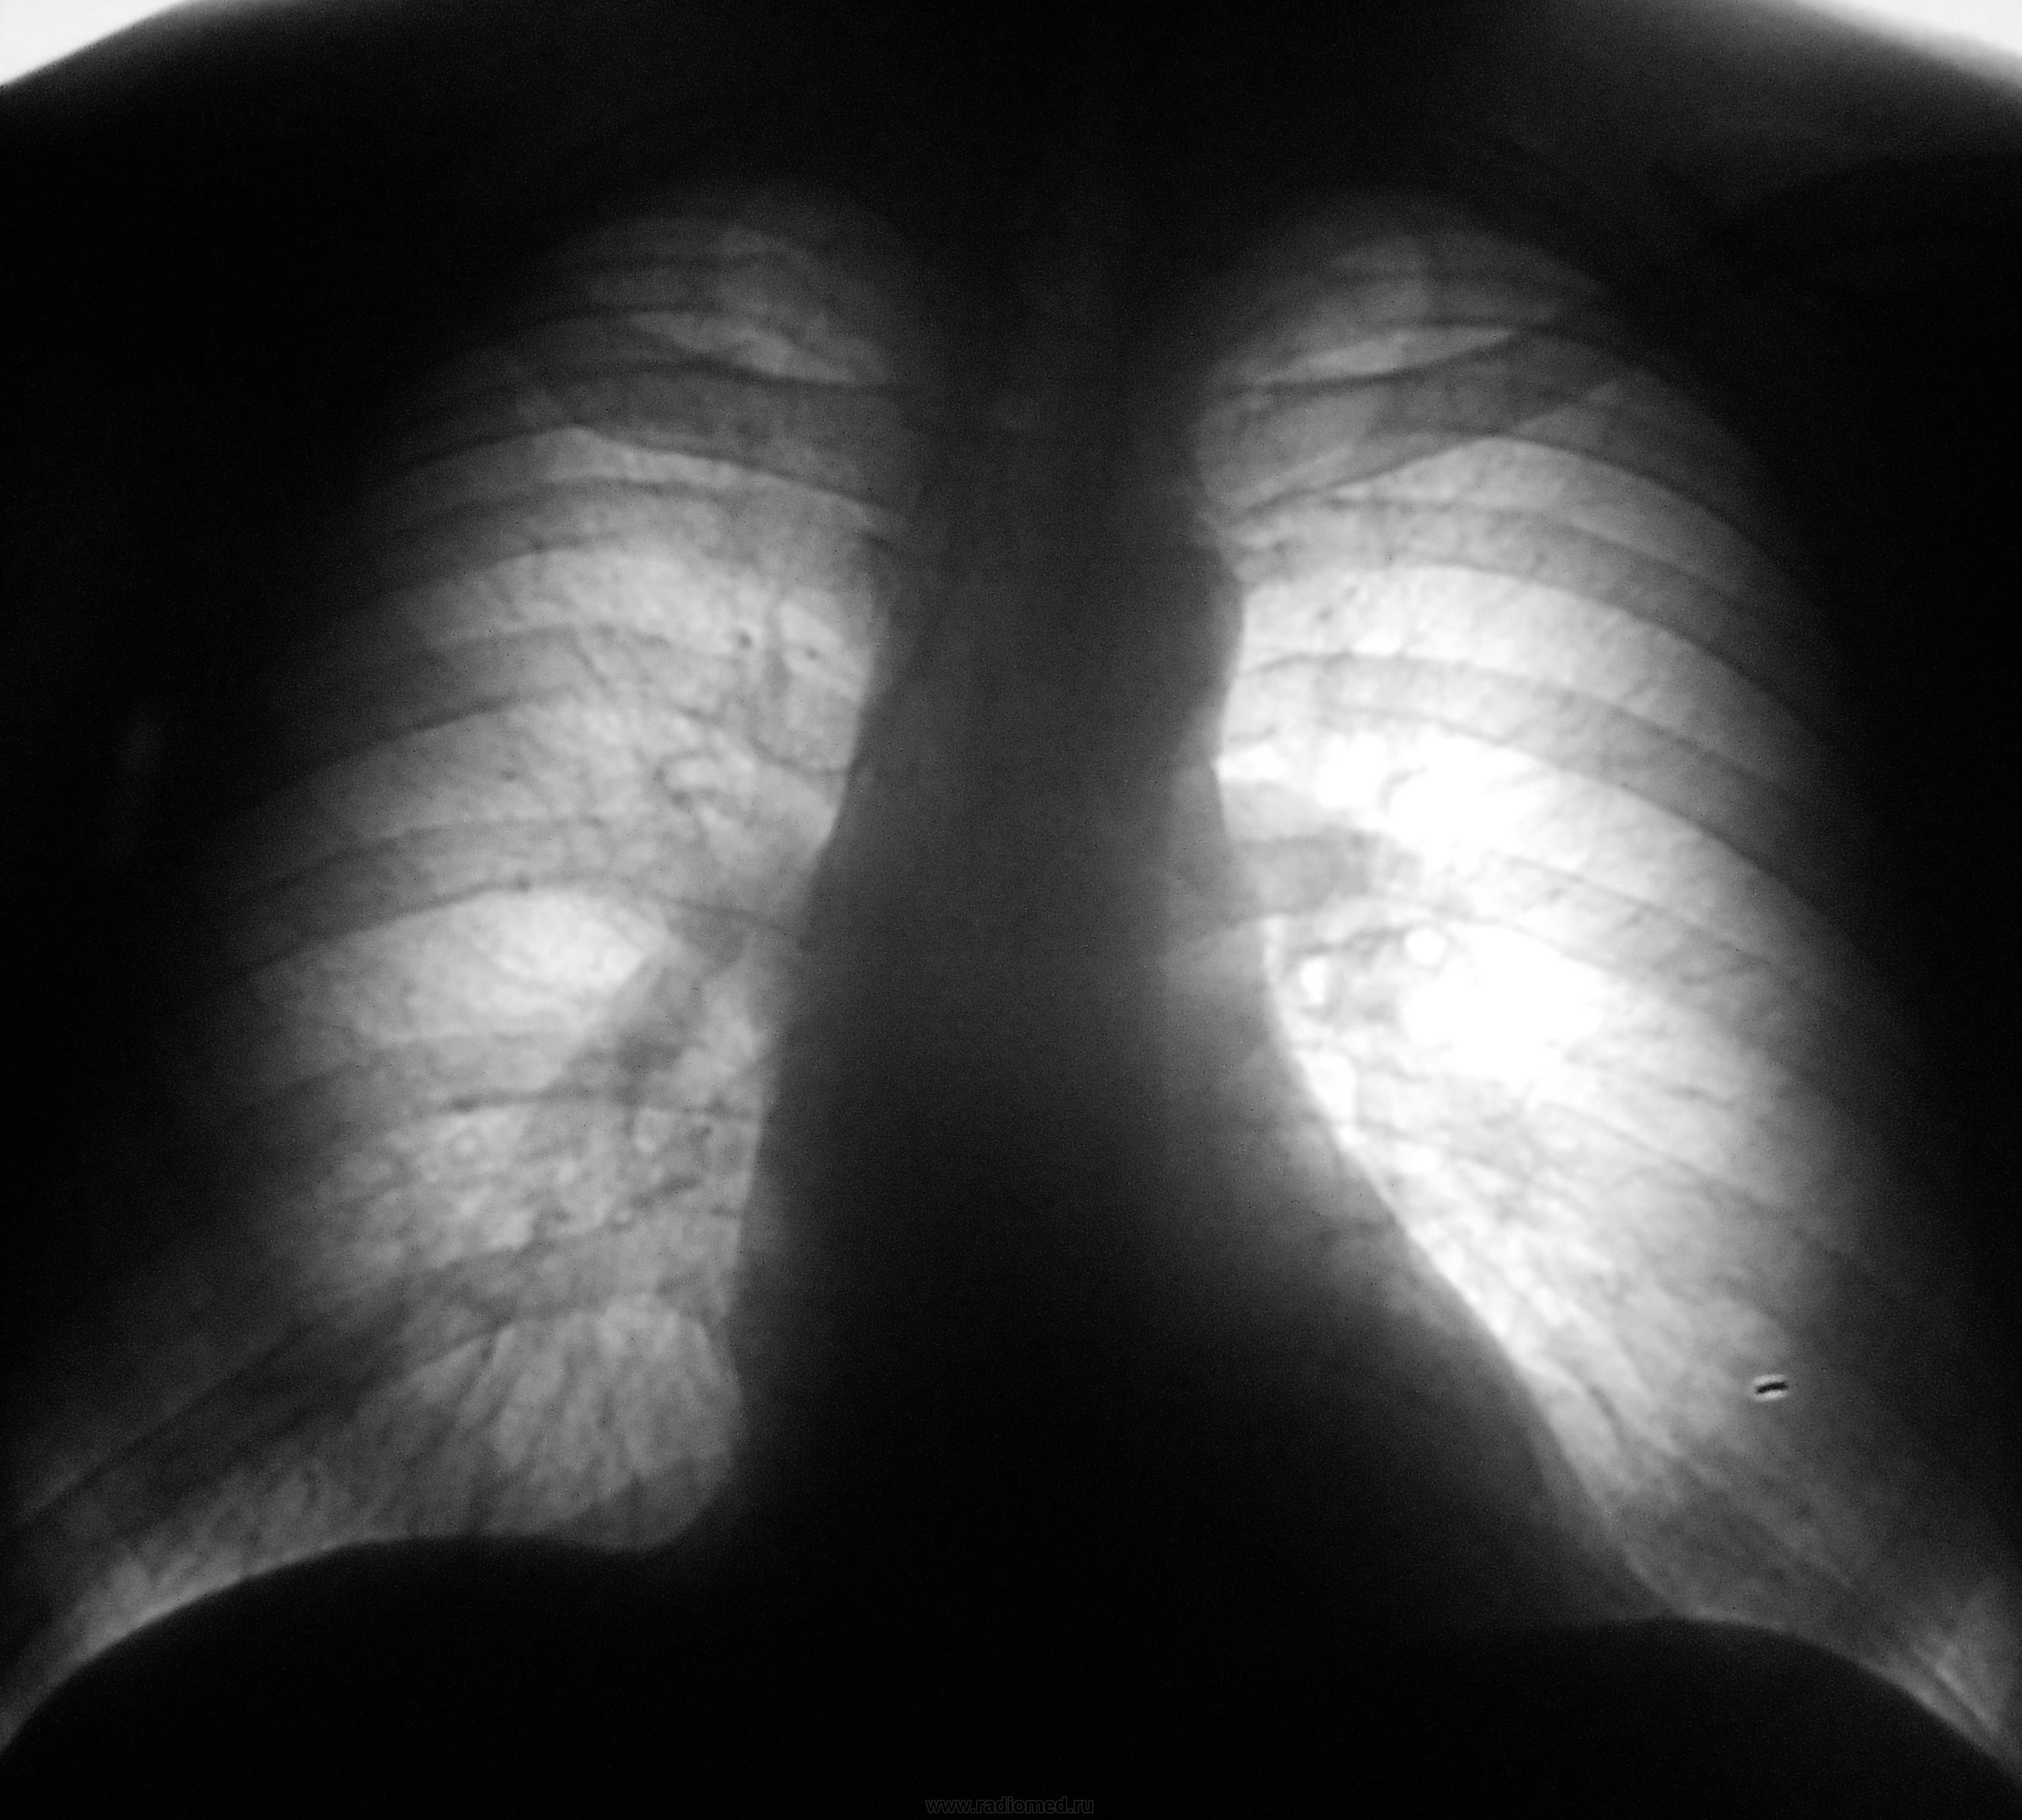

Левое легкое смотрится слишком воздушным, верхушки легких тоже не очень нравятся

Логично предположить объем в правом легком, а слева викарную эмфизему. Но это уже в течение года? Боковые, ТМГ на бочку! Возраст?

Пока тянет на "зло". Центральный в/долевой, медиастинальный. Смущает возраст, отсутствие жалоб (в последнем я сомневаюсь).

Пациент был направлен на профилактическую флюорографию (плановую), работает "на пищевом предприятии". Лаборант флюорографа сделал снимок. увидел "непорядок" и позвал меня. Сразу забрали в рентгеновский кабинет, сразу дообследовали..., поговорили.., да есть одна жалоба, что когда дома снегуа много покидает (у нас в этом году снега немерено), так "задышка" у него появляется, но, он сам связывает эту жалобу с физической нагрузкой.

Не так давно был случай - женщина 60 лет - картина примерно такая же, на вид все ок, жалоб нет. Впоследствии подтвержден центральный рак легкого

Центральный рак вряд ли. Какая-нибудь лимфома.

к флюорограмме, то можно сейчас обратить внимание на тень, которую я отметил на рисунке. Так ли это? Поддерживаю мнение Игоря Ивановича.

Тень исходит из переднего средостения, "нависает", если можно так выразиться преимущественно над правыми отделами сердца (слева средостение "выпирает" в значительно меньшей степени . Главные бронхи проходимы, но сдавлены из-вне пакетами л/узлов (слева корень неспокоен, но в меньшей степени). Не могу понять происхождение  тени, дифференцирующейся на ТМГ слева на фоне сердечных камер. Согласна с Nikolas, на первом снимке дифференцируется дополнительная дуга по правому контуру. Очень похоже на ЛГМ, возможно, неходжкинская лимфома.

Мне кажется, что поражены л/узлы справа, бифуркационные, переднего средостения. Скорее всего , дейстительно, выскочит лимфома.

На предудущей флюорограмме, действительно, по правому контуру сердца есть дополнительная тень выходящаяя за контур:  "симптом кулис",  но  его легко принять  за особености расположения сосудов. Иногда в этом месте может быть дополнительная дуга  восходящего отдела аорты, но тень должна быть однородной, без второго контура.